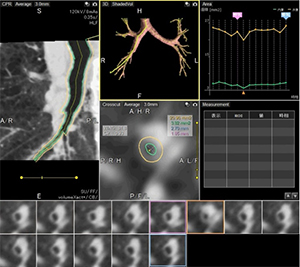

4D脳動脈形態計測

1.4D脳動脈形態計測

未破裂動脈瘤の治療を行う術前評価として,動脈瘤形状を自動で計測し各種パラメータを算出することで,治療選択のサポートを行える。さらに従来は目視に頼っていた動態の評価から,連続して収集した各情報から位相ごとに色を付けて重ね合わせることができ,ブレブの拍動部位の色分けや計測が行えるため,どのように変化しているか評価が可能となり,未破裂動脈瘤の破裂リスクの予測など期待できる。

2.4D気管支トラッキング

気管支の病変を連続して収集した情報から,呼吸による動態での解析が可能となる。気管支の自動抽出と自動位置合わせを行いながら,位置の移動量を考慮し観察したい任意断面を4Dで表示が可能なため,任意気管支断面の内腔や外壁の面積,最大・最少径など算出し,気流制限があるかなど病変発見に期待ができる。